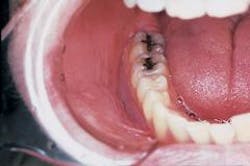

Intraoral examination revealed a large, diffuse white area in the mucobuccal fold (see photo). The lesion appeared wrinkled or corrugated in texture. The lesion could not be removed by wiping or scraping. Further oral examination of the oral soft tissues revealed no other lesions present.

Although a smokeless tobacco keratosis is typically seen in young males, this lesion may be seen in any individual who uses a smokeless tobacco product. The lesion has a fairly characteristic clinical appearance and is found at the preferred site of tobacco placement. If more than one intraoral location is used to hold the tobacco products, multiple and less prominent lesions may be seen. The most frequent sites of involvement include the mucobuccal fold area in the incisor and molar regions.

The typical smokeless tobacco keratosis appears white with a raised or flat contour. The texture of the lesion appears smooth, granular, or corrugated. The appearance of the keratosis has been compared to that of an "ebbing" tide. A smokeless tobacco keratosis is asymptomatic and is usually discovered upon routine oral examination.